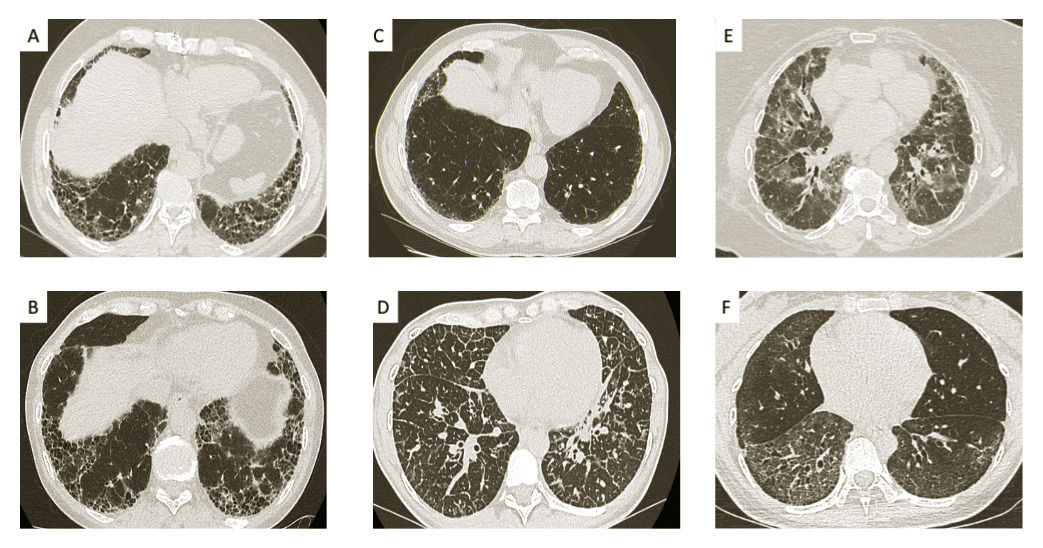

Le scanner thoracique est l’examen essentiel au diagnostic. Il doit être de qualité irréprochable et analysé par un radiologue ayant une expertise dans le domaine des pneumopathies interstitielles. Il identifie les signes de fibrose (fig. 1A et 1B ) qui associent des réticulations et des bronchectasies par traction affectant les bronches distales, éventuellement des opacités en rayon de miel, une perte de volume des lobes atteints et des distorsions des structures anatomiques (bronches, plèvre…).

Lorsque l’ensemble de ces signes est réuni, avec une prédominance des anomalies dans les régions sous-pleurales et dans les lobes inferieurs, on parle d’un aspect typique de pneumopathie interstitielle commune (PIC). Cet aspect est retrouvé dans 50 à 70 % des cas de FPI.

En l’absence de rayons de miel, les bronchectasies par traction associées aux réticulations permettent de parler de PIC probable (fig. 1C ).1

Dans tous les autres cas, lorsque l’aspect du scanner n’est pas caractéristique de PIC (fig. 1D à 1F ), le diagnostic de certitude nécessite une biopsie pulmonaire.